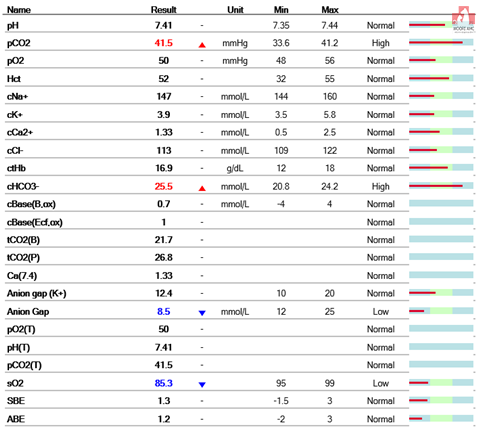

먼저 마취전 검사를 하기로 했어요.

다행히 혈액검사상으로는 탈장에 의한 근 손상으로 AST, CK가 올라간 것 이외의 특이 소견은 없었습니다.

그러나 혈액 검사 상 신장의 수치는 양호하고 마취에 관해서는 괜찮다고 생각됩니다.